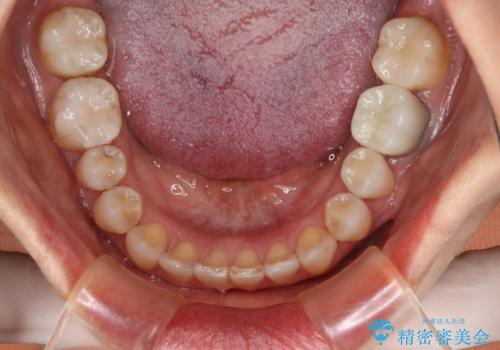

- 右上の小臼歯が二本とも90度捻じれてしまっており、奥歯の噛み合わせに問題が生じていました。

歯を抜いてワイヤー治療を行うという選択肢もありましたが、

奥歯の被せ物の形を適切にすることで非抜歯でも治療が可能であると判断し、

非抜歯、インビザラインでによるマウスピース矯正治療を行うことにいたしました。

今回は右上の奥歯に入っていた銀歯の形が悪く、そのせいで歯を並べるスペースが足りない状態でした。

右上の歯の被せ物を作りなおし、適切な歯の大きさに代えてあげることによってスペースを作りました。

また、それだけではスペースが足りない為右上の奥歯は遠心移動を行っています。